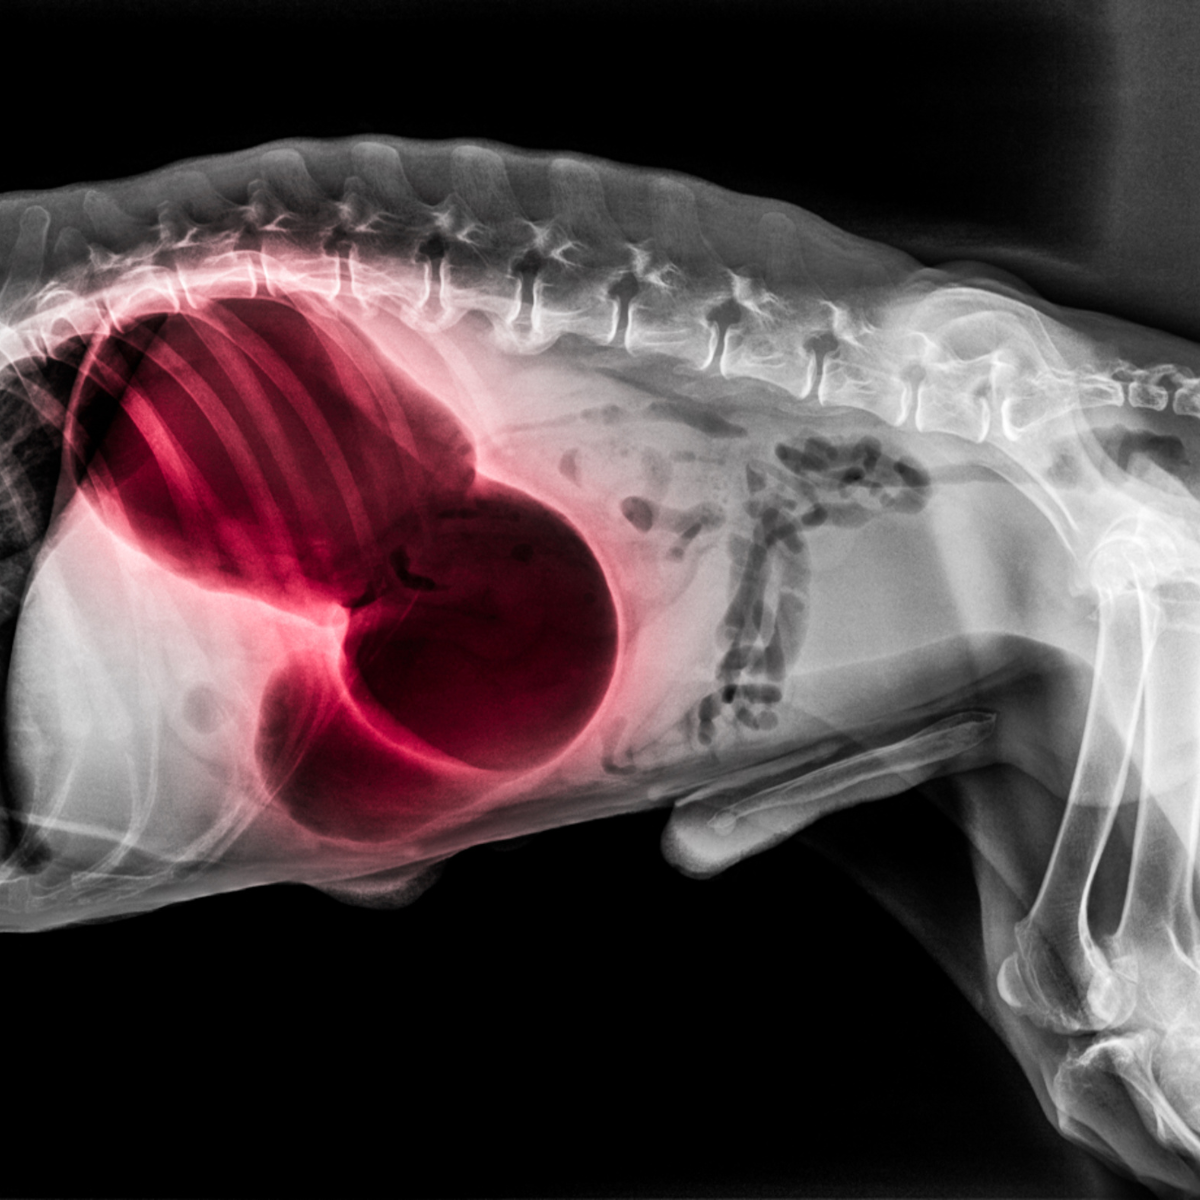

- Ocena kliniczna – Weterynarz przeprowadzi szybką ocenę kliniczną, aby potwierdzić diagnozę. Często stosuje się zdjęcie rentgenowskie, które pokaże charakterystyczne powiększenie i przesunięcie żołądka. W zależności od stopnia zaawansowania stanu, mogą być również wykonane badania krwi, aby ocenić stan ogólny psa oraz wpływ skrętu na funkcje narządów wewnętrznych.